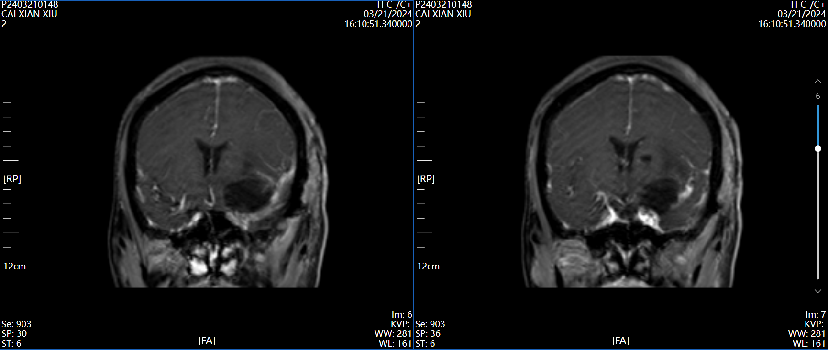

术后第3天磁共振增强  2024.03.21